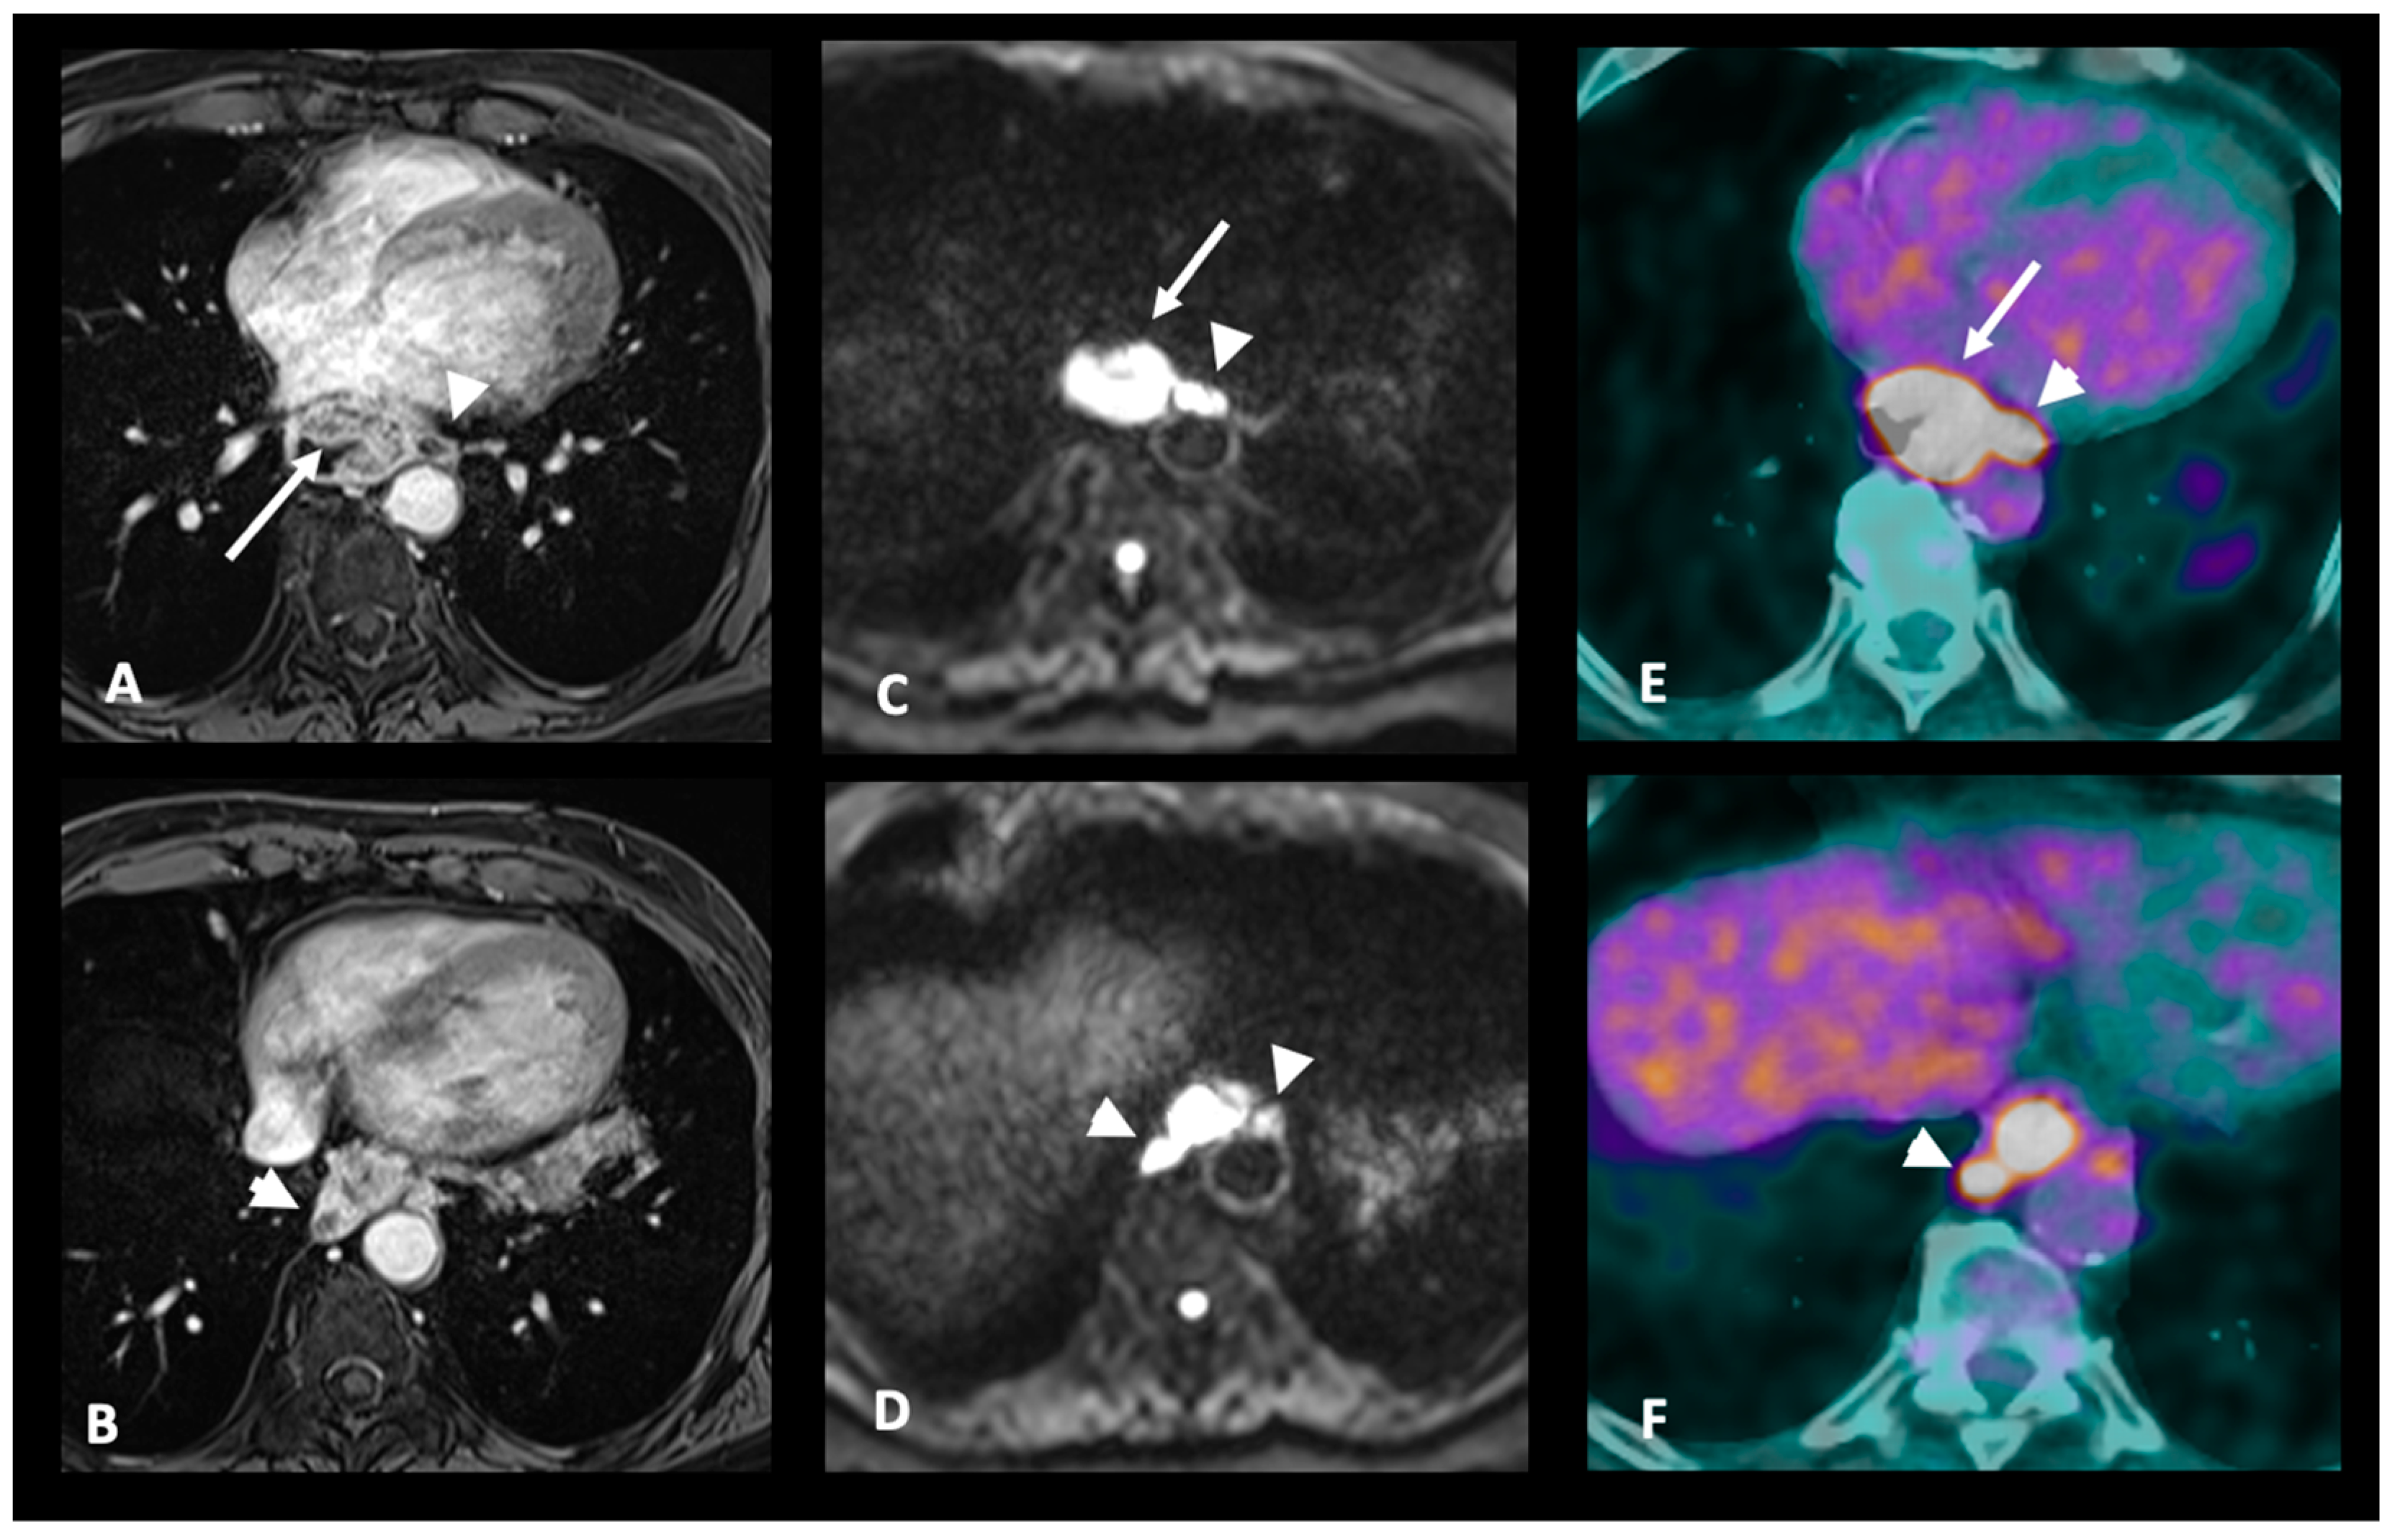

3.3. M Staging

| M+: Distant metastases | MRI-M+: Distant lymph node (sus-clavicular e.g.), liver metastases or other organ metastases |